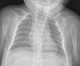

Sprengel's deformity (also known as high scapula or congenital high scapula) is a rare congenital skeletal abnormality where a person has one shoulder blade that sits higher on the back than the other. The deformity is due to a failure in early fetal development where the shoulder fails to descend properly from the neck to its final position. [Source: Wikipedia ]